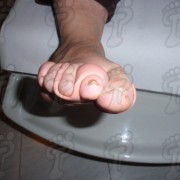

Hoy quiero compartir con vosotros, uno de los casos de metástasis acral que me he encontrado a lo largo de mi carrera profesional. He seleccionado este caso por el compendio de características que reúne en sí la lesión (color, aspecto, textura, etc.) Se trata de una paciente octogenaria afectada de un tumor primario en el colon con metástasis hepática y acral. Este caso lo recuerdo muy especialmente debido a la agresividad y rápida evolución de la patología.

Necesito de ayuda, ya que mi mama tiene lo mismo que esta persona que esta en la fotografia, aunque lo de ella es unas tres veces mas grande, no sabemos que hacer, necesitamos de informacion urgentemente, gracias por sus comentarios.

Dr mi esposo tiene así su pie se puede hacer cirugia

Tengo como un bulto en la parte de la. planta del pie derecho, me duele mucho al caminar de echo ni pisar puedo porque me duele todo el pie, es como color amarillo y agrietado